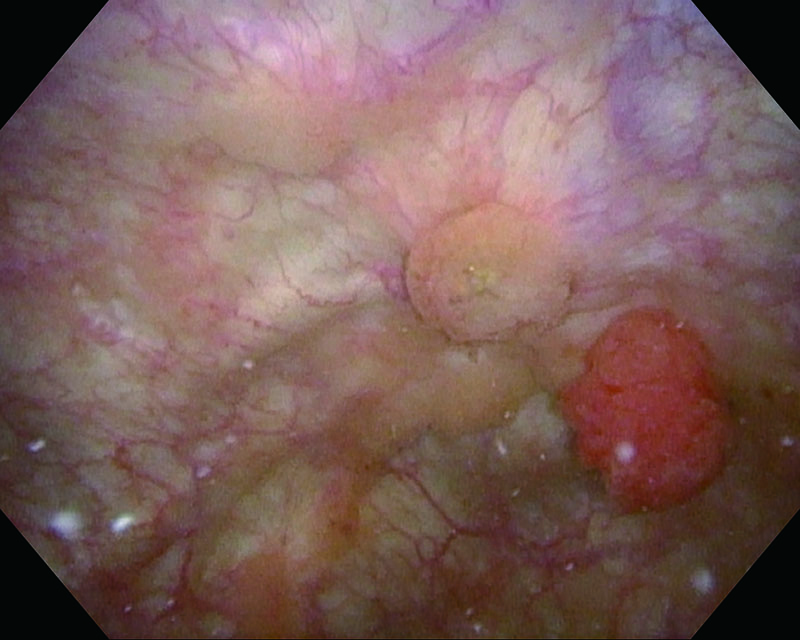

Mucosa avermelhada, homem de 81 anos

Luz branca

NBI

Histologia UC, CIS

Comentários

CIS de bexiga. O uso do NBI nos permitiu aprimorar a visualização da região marginal.